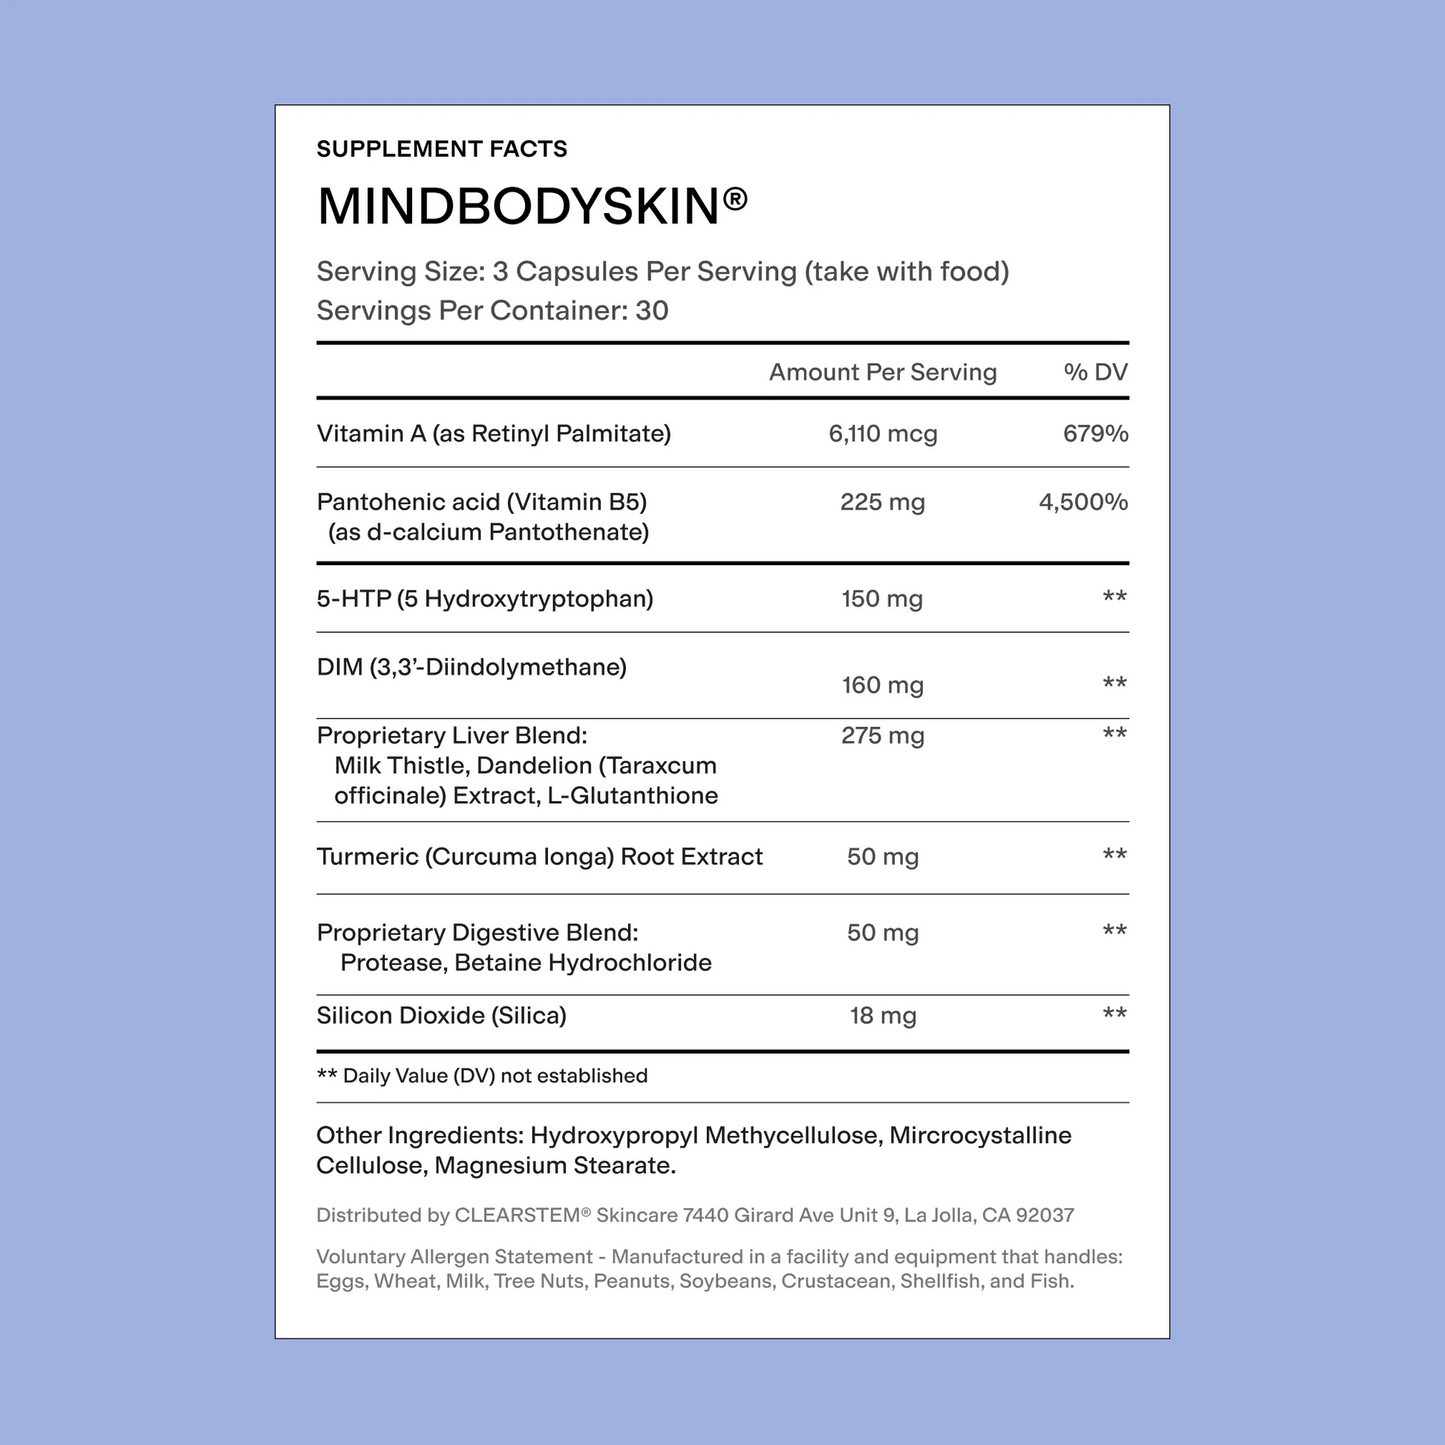

GOOD FOR

Oil Control, Skin Cell Turnover, Detoxification

SERVING SIZE

3 Capsules

WHEN TO USE IT

Take daily with food

KEY INGREDIENTS

Bioavailable Vitamin A, DIM, B5, Turmeric, Dandelion Root, 5-HTP, Glutathione